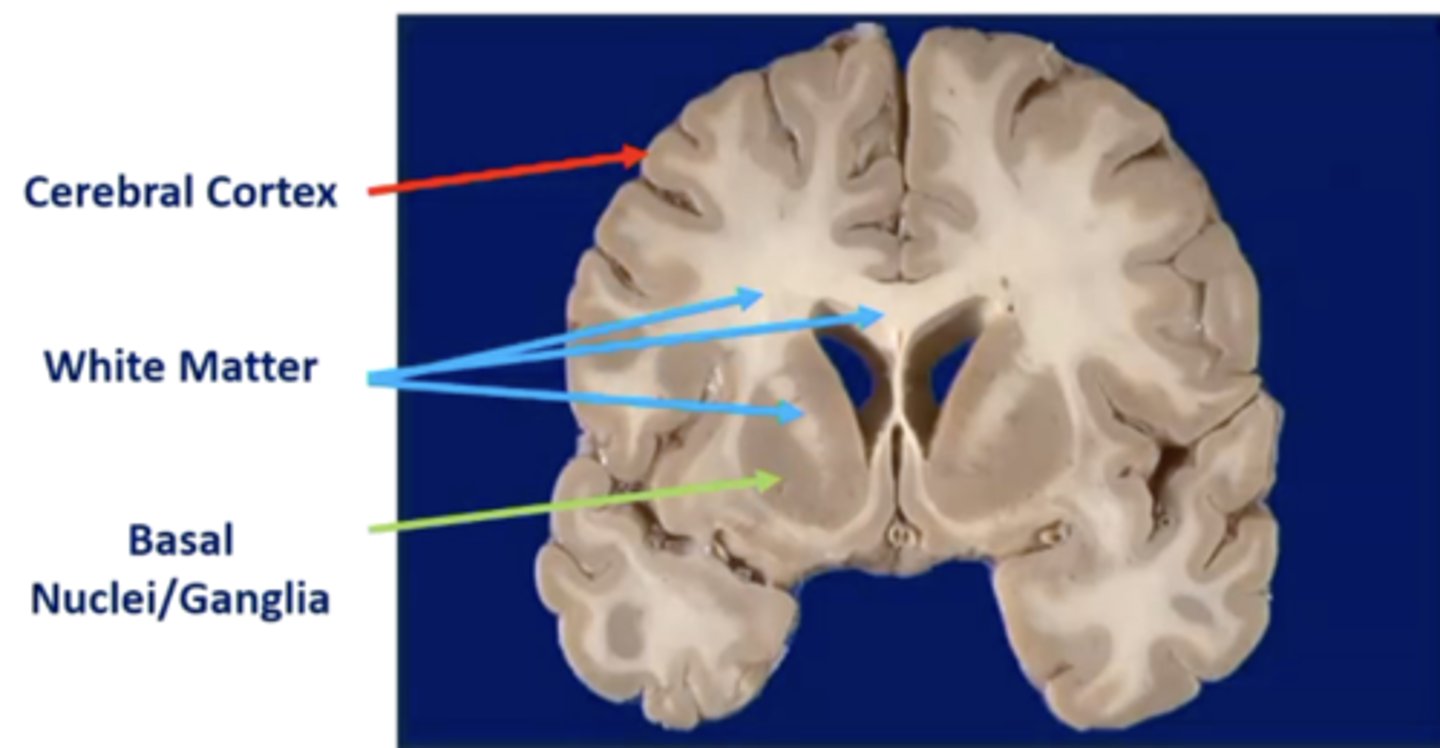

what is the cerebral cortex?

thin, wrinkled outer layer of gray matter tissue covering the brain

what is the function of the basal ganglia?

modulate movement and posture

what are the basal ganglia nuclei (5):

1. caudate nucleus

2. putamen

3. globus pallidus

4. substantia nigra

5. subthalamic nucleus